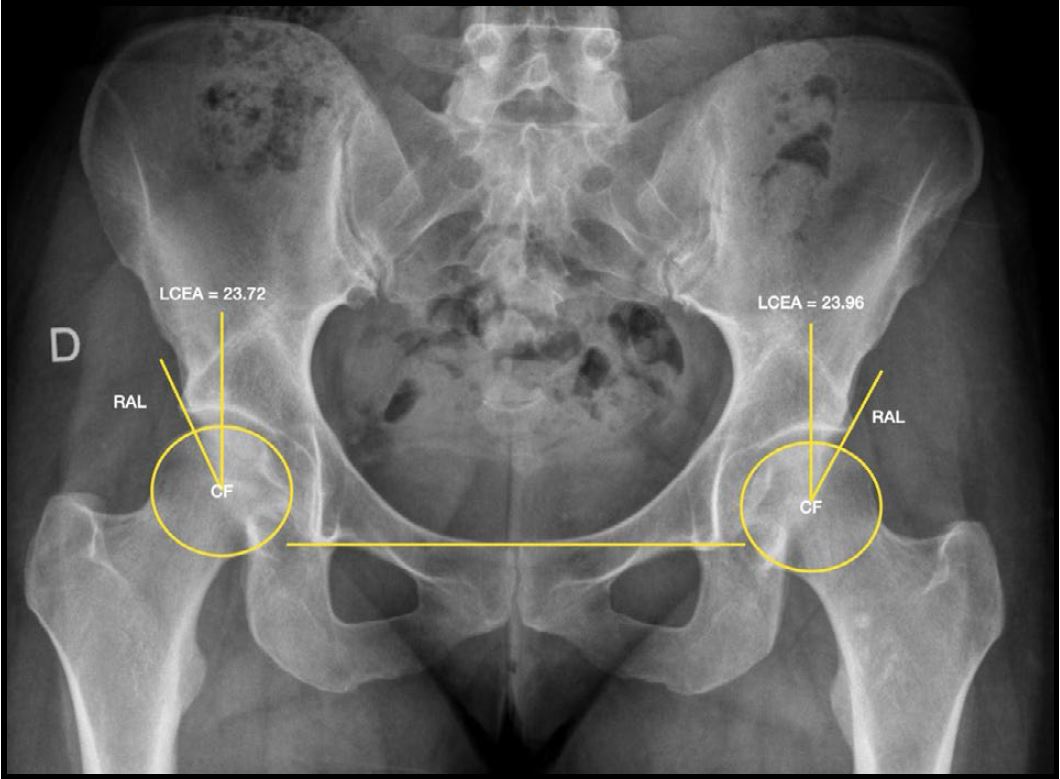

La evaluación por imágenes incluyó radiografías de pelvis anteroposterior, proyección de Lowenstein y de Dunn, resonancia nuclear magnética (RNM) de al menos 1.5 Tesla con cortes acetabulares radiales, y tomografía computada con reconstrucciones radiales para la evaluación detallada de deformidades femorales y acetabulares mediante mediciones angulares con distribución horaria. El punto de corte para el diagnóstico de displasia limítrofe fue un ángulo centro-borde lateral (LCEA de Wiberg) entre 20° y 25° (Fig. 1). La RNM fue utilizada para la detección de patología labral y/o condral asociada (Fig. 2). Las características demográficas y clínicas de la muestra se detallan en la Tabla 1.

Figura 1. Radiografía A-P de pelvis que muestra la medición del ángulo centro-borde lateral (LCEA de Wiberg) en ambas caderas. Se señalan el centro de la cabeza femoral (CF) y el reborde acetabular lateral (RAL) como referencias anatómicas para la medición del ángulo de cobertura acetabular.

Resultados radiográficos

Las evaluaciones radiográficas incluyeron la medición del ángulo alfa, el ángulo de Tönnis y el ángulo centro-borde lateral (LCEA). El primero presentó una media de 61.3° ± 6.2° en el preoperatorio, que disminuyó a 53.7° ± 5.1° a los 2 años de seguimiento; la reducción es estadísticamente significativa (p <0.004).

No se observaron cambios clínicamente relevantes en el ángulo de Tönnis ni en el LCEA durante el período de seguimiento.